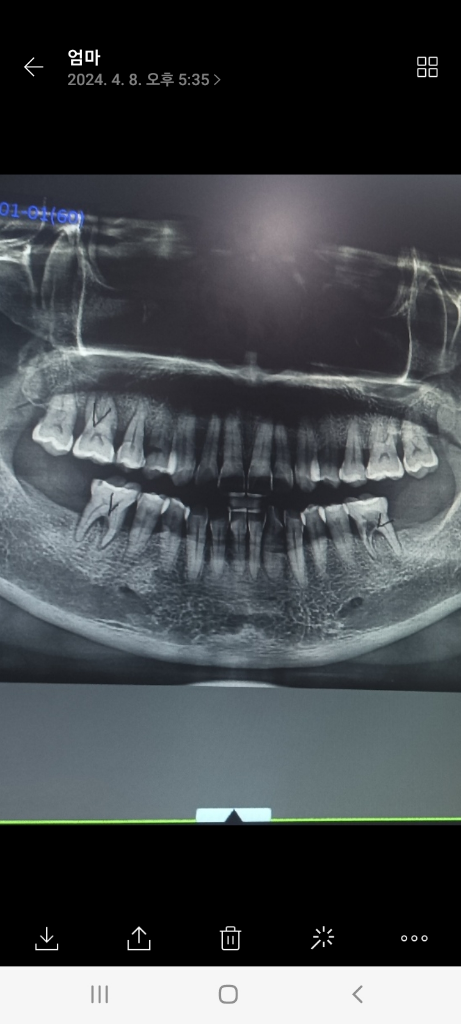

뼈가 다 녹아서 임플란트가 안된다고 하는 곳도 있고 뼈 이식고 받아야 한다네요

Q.치료방향을 어떻게 잡아야 할지 조언좀 부탁드려요. 임플란트 틀니 브릿지

일단 임플란트 시 뼈 이식이 필요할지 판단에는 2차원 파노라마 방사선 사진보다도 3차원 CT가 필요합니다. 술식이 들어가셔야 뼈 이식이 필요함을 알 수 있는 경우도 있습니다.

현재 임플란트를 식립하기에 치조골이 부족한 상태로 뼈이식을 하고, 임플란트 진행은 가능합니다.

아래쪽은 잇몸뼈가 충분해서 크게 어렵진 않겟지만, 오른쪽 위 치아는 잇몸뼈에 염증이 많아서 뼈이식이 필요할수도 잇을것같습니다.